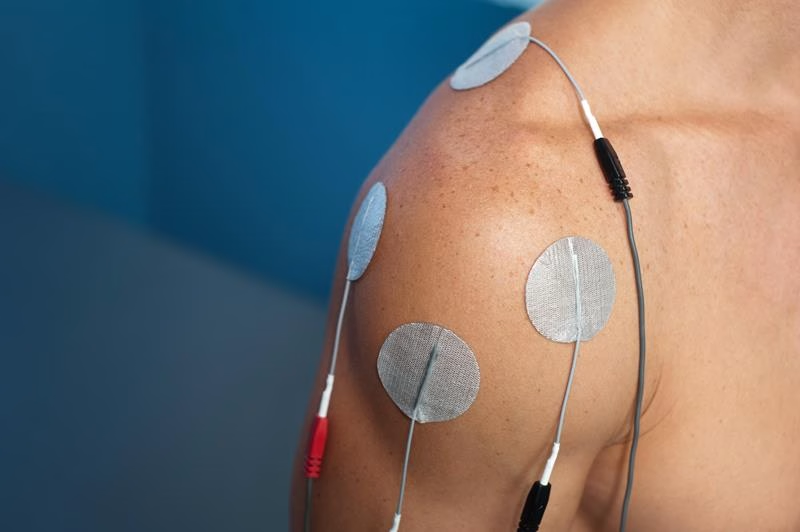

E-Stim therapy works by delivering low-level electrical currents through electrodes placed on the skin over the treatment area. These currents interact with the body’s own bioelectrical system to produce a range of therapeutic effects depending on the frequency, intensity, and waveform of the current applied. When electrical stimulation passes through injured or dysfunctional tissue, it produces thermal, physiological, and chemical responses that support healing and pain relief.

At Avalon Chiropractic Healing Center, the most commonly used form of electrical stimulation is interferential current (IFC) therapy. This technique uses two separate channels of electrical stimulation that intersect within the treatment area, creating a third “interferential” current that penetrates deeply into the affected tissues with minimal resistance at the skin surface. This allows therapeutic electrical current to reach structures well beneath the skin — including deep muscles, joints, and nerve pathways — that superficial electrical stimulation cannot adequately address. The result is effective pain control, muscle relaxation, and improved circulation without discomfort at the skin surface.